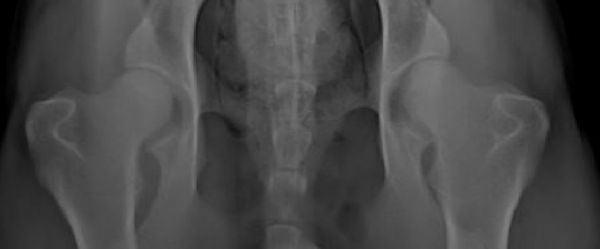

Look at these hips. These are x-rays of the same female taken at two different vets /don´t care about two names in the pictures - Axa in the 1st and Sheila in the second,she was called Axa by her 1st owner,now she is called Sheila/.

these hips graded as good.